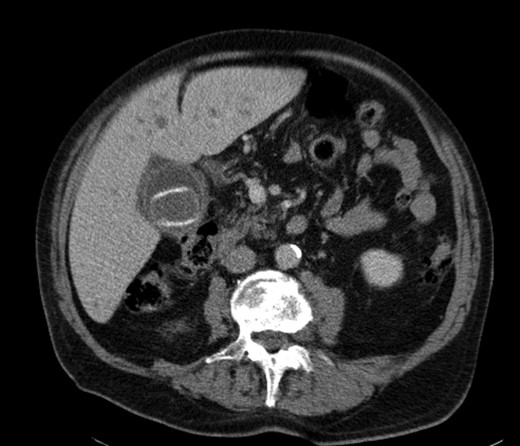

A 92-year male, with no significant co-morbidities apart from peptic ulcers, was admitted with 6 days of obstination. On examination he was dehydrated, with a hugely distended abdomen but no signs of peritonitis. Blood showed features of dehydration and plain abdominal X-ray demonstrated both small and large bowel dilatation, but no obvious causal pathology. A contrast-enhanced computed tomography scan revealed a 2.5-cm partially calcified gallstone impacted at the descending colon-sigmoid junction (Fig. 1). There was no stricture or diverticular disease distal to the stone. A cholecysto-colic fistula could be seen (Fig. 2), with a further smaller gallstone in the caecum (Fig. 3). The offending gallstone could be seen incidentally in the gallbladder on imaging 3 years previously (Fig. 4).

The offending gallstone as an incidental finding 3 years previously.